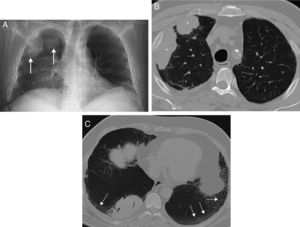

We present the case of a 66 year-old patient who presented at surgery with dyspnoea. A chest X-ray revealed multiple opacities in the right lung (Fig. 1A). Of note in the patient's medical history was high blood pressure, type 1 diabetes mellitus (both controlled), and nonspecific interstitial pneumonia (NSIP) which had been confirmed several years previously by means of a biopsy. Computerised tomography (CT) of the chest confirmed the presence of multiple right lung masses (Fig. 1B), with aerial bronchogram, with no pleural or lymph node effusion, and with interstitial involvement (Fig. 1C). Transbronchial biopsy confirmed high grade diffuse large B-cell non-Hodgkin lymphoma (DLBCL). Positron emission tomography/CT (PET/CT) ruled out other tumours. The patient was treated with chemotherapy (R-CHOP regimen), with complete response after 6 cycles.

(A) Posteroanterior X-ray of the chest in which several nodular opacities are observed in the right lung (arrow). Note the presence of a subtle bibasal enlargement of the lung interstitium. (B) Axial image of chest CT which confirms the presence of right lung masses (asterisks). (C) Axial image of chest CT (minimum intensity projection) in which a bibasal lung interstitium reticulation (arrows) may be observed in relation to the patient's interstitial lung disease. Note the presence of small traction bronchiectasis.